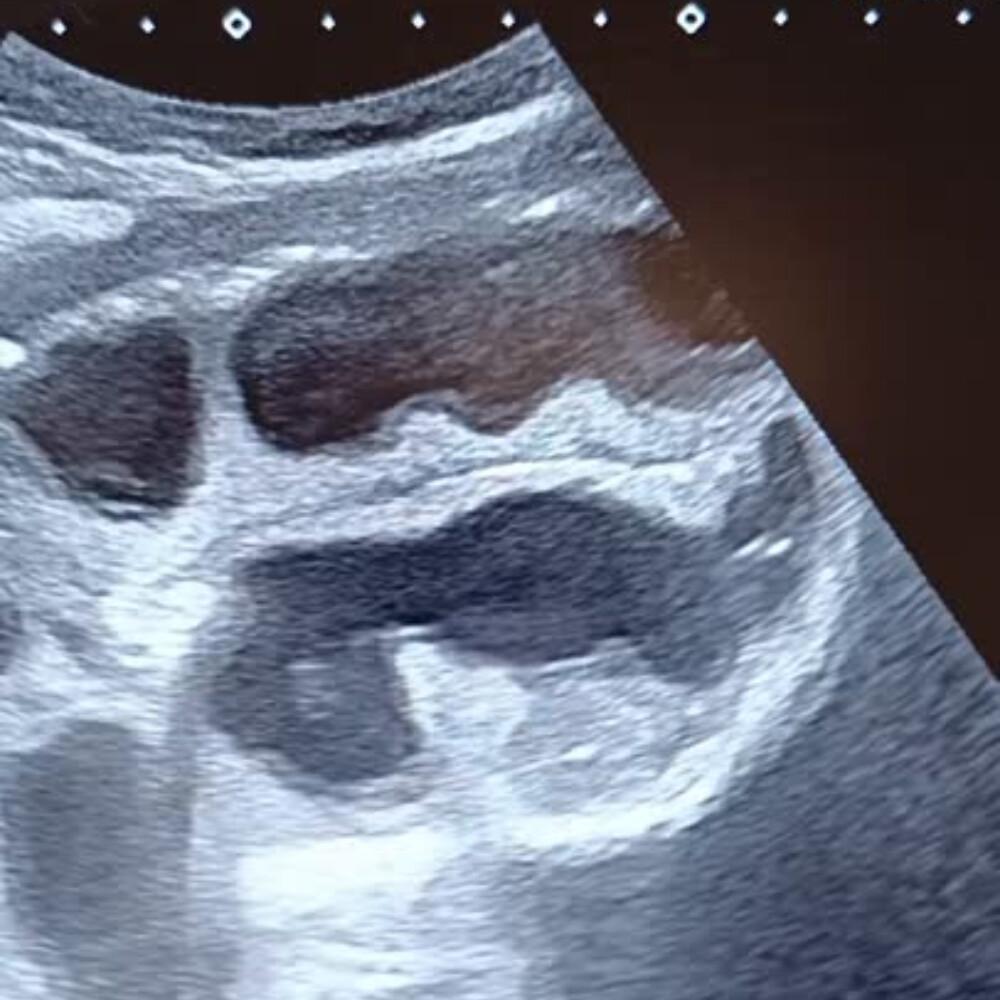

- Dilatation des anses grêles : diamètre > 25 mm (> 2,5 cm), contenu liquidien, paroi fine.

- Anses coliques : plus périphériques, contenu gazeux, haustrations visibles.

💧 Rechercher un épanchement inter-anse : marqueur de souffrance digestive.